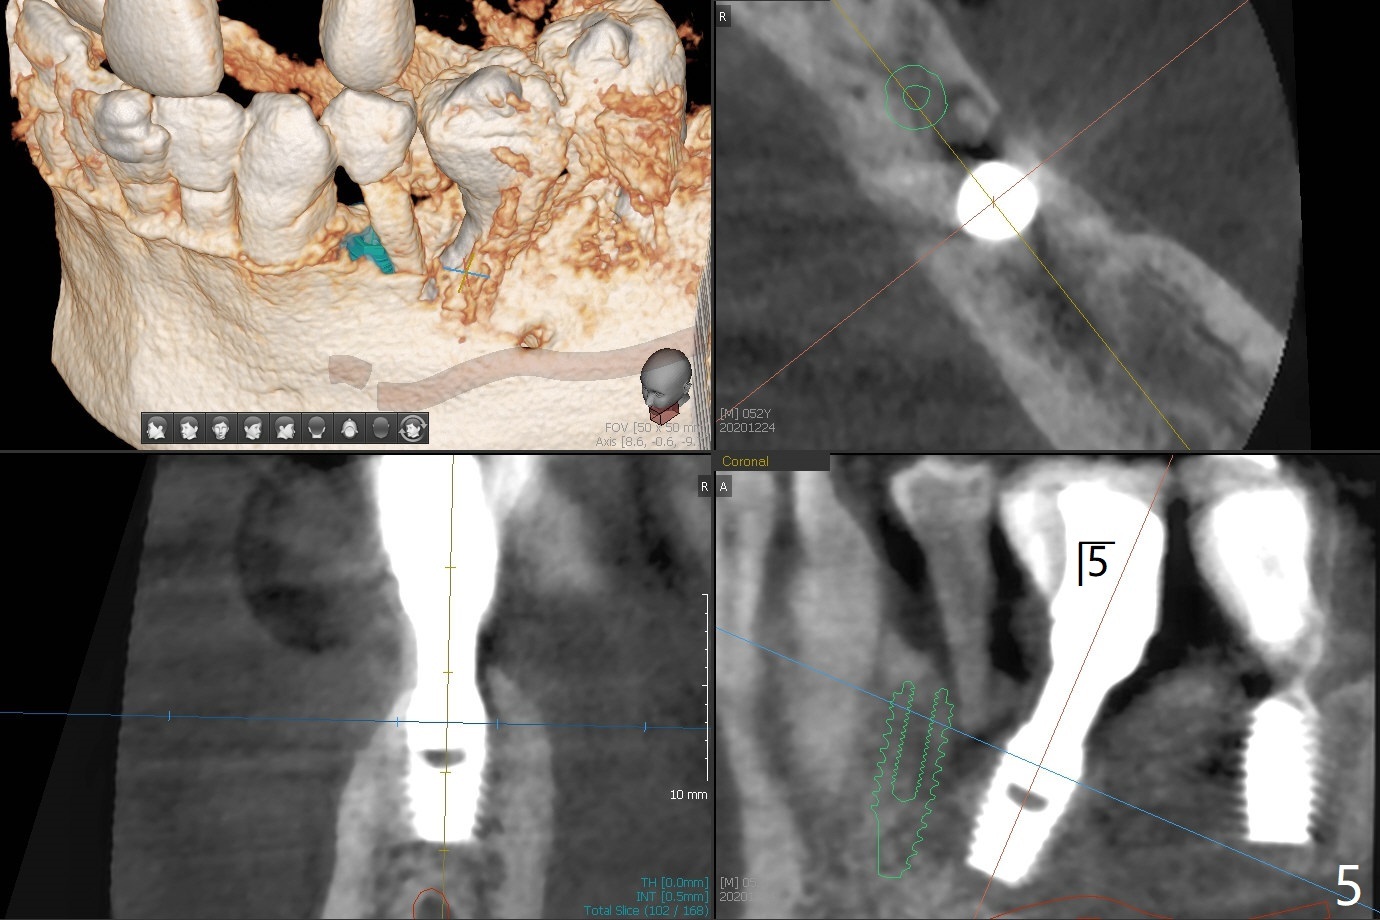

52岁男右下4植体脱落,植骨后,使用左侧咀嚼,发现左下4松动(图一,二),无法吃饭,认为必须拔除植牙(图三,四),徒手种植的邻近植体位置不好,但无骨质吸收(图五,六(牙冠粘固后9年10月)),4种植必须用导板